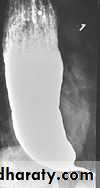

Esophageal diverticulum

Zenker diverticulumTraction

Epiphrenic diverticulum